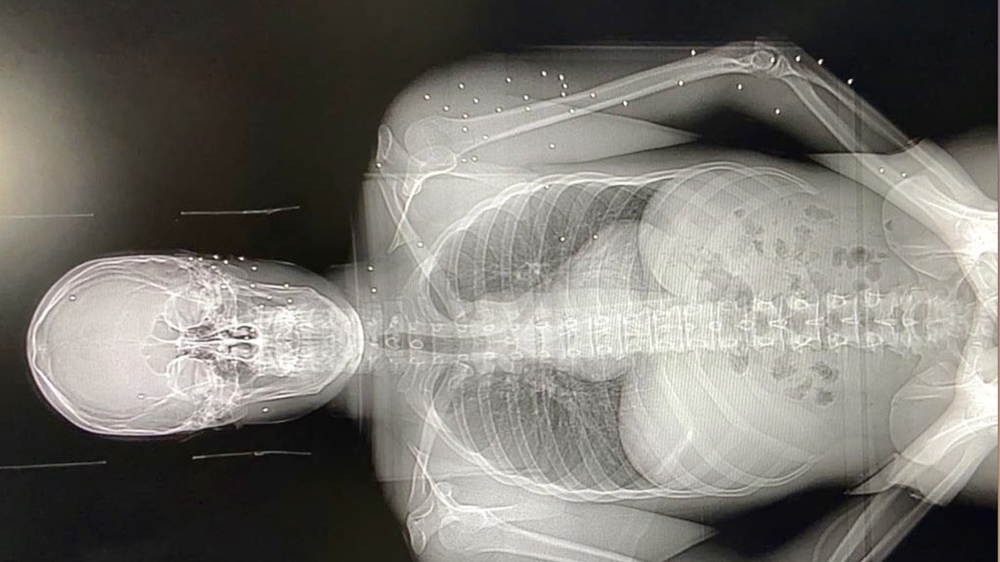

At least 728 people were injured during Saturday’s protest, including many receiving wounds to head, neck and chest. Wounds were consistent with both rubber bullets and birdshot.

One patient was brought in with at least 50 pellets spread across his body.